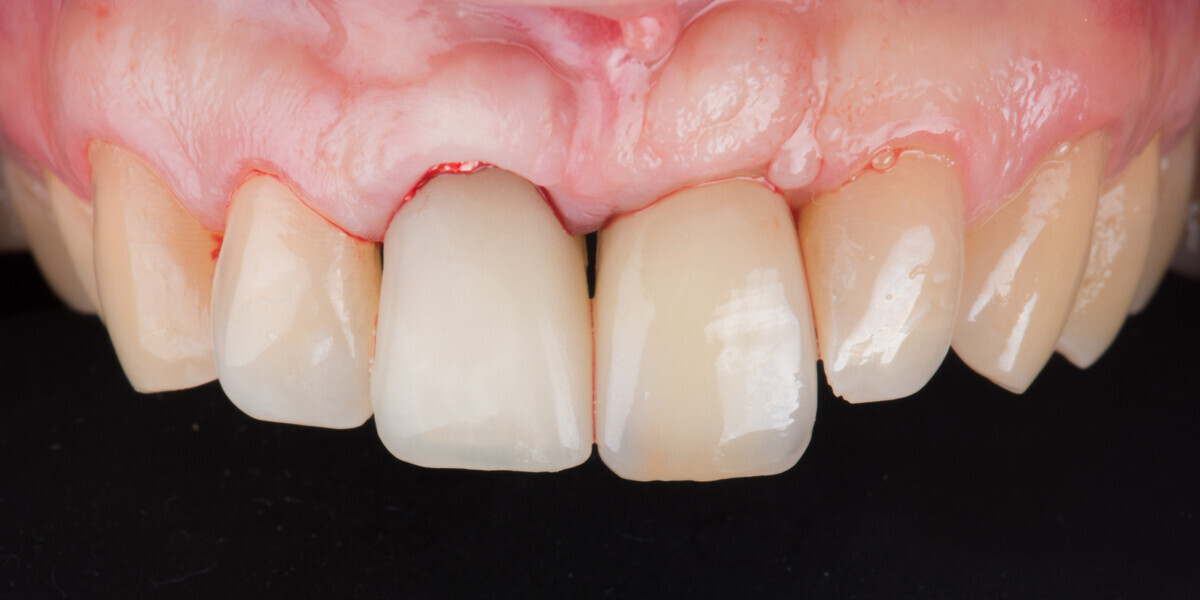

Immediate placement and restoration of a Straumann BLX implant replacing maxillary incisors